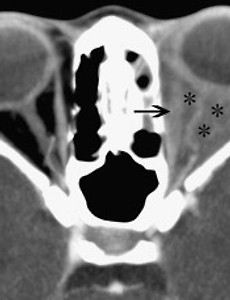

하지 정맥류가 눈에 발생하는 경우, 안와 정맥류, Orbital Varix, Orbital varices 안와 정맥류는.. 매우 드물게 발견되는 질환으로, 만성적인 안구 돌출의 원인중의 하나 입니다. 이때 안구 돌출이란 항상 안구가 돌출되는 것이 아닌, 간헐적인 안구 돌출(intermittent proprolapse)로써, 복압 상승으로 유발되는 간헐성 안구 돌출의 90%를 차지한다고 알려져 있습니다. 주로 아동기와 청소년기에 안구 돌출을 초래하며, 복압이 상승하여, 경정맥압이 상승하는 경우 뚜렷한 안구돌출을 관찰할수 있습니다. 발살바법을 시행하거나, 울고난뒤, 배에 힘을 주고 나면, 복압이 상승하고, 목의 정맥압이 상승하여, 정맥류속의 혈류가 저류되면서 정맥류의 크기가 커지게 되는 원리입니다. 안와 정맥류는 주로 단안에서 발생하며 때로는 같은쪽 얼굴이나 눈꺼풀, 코안, 입안에서도 비슷한 정맥류 병변을 관찰.. 2018. 9. 9.